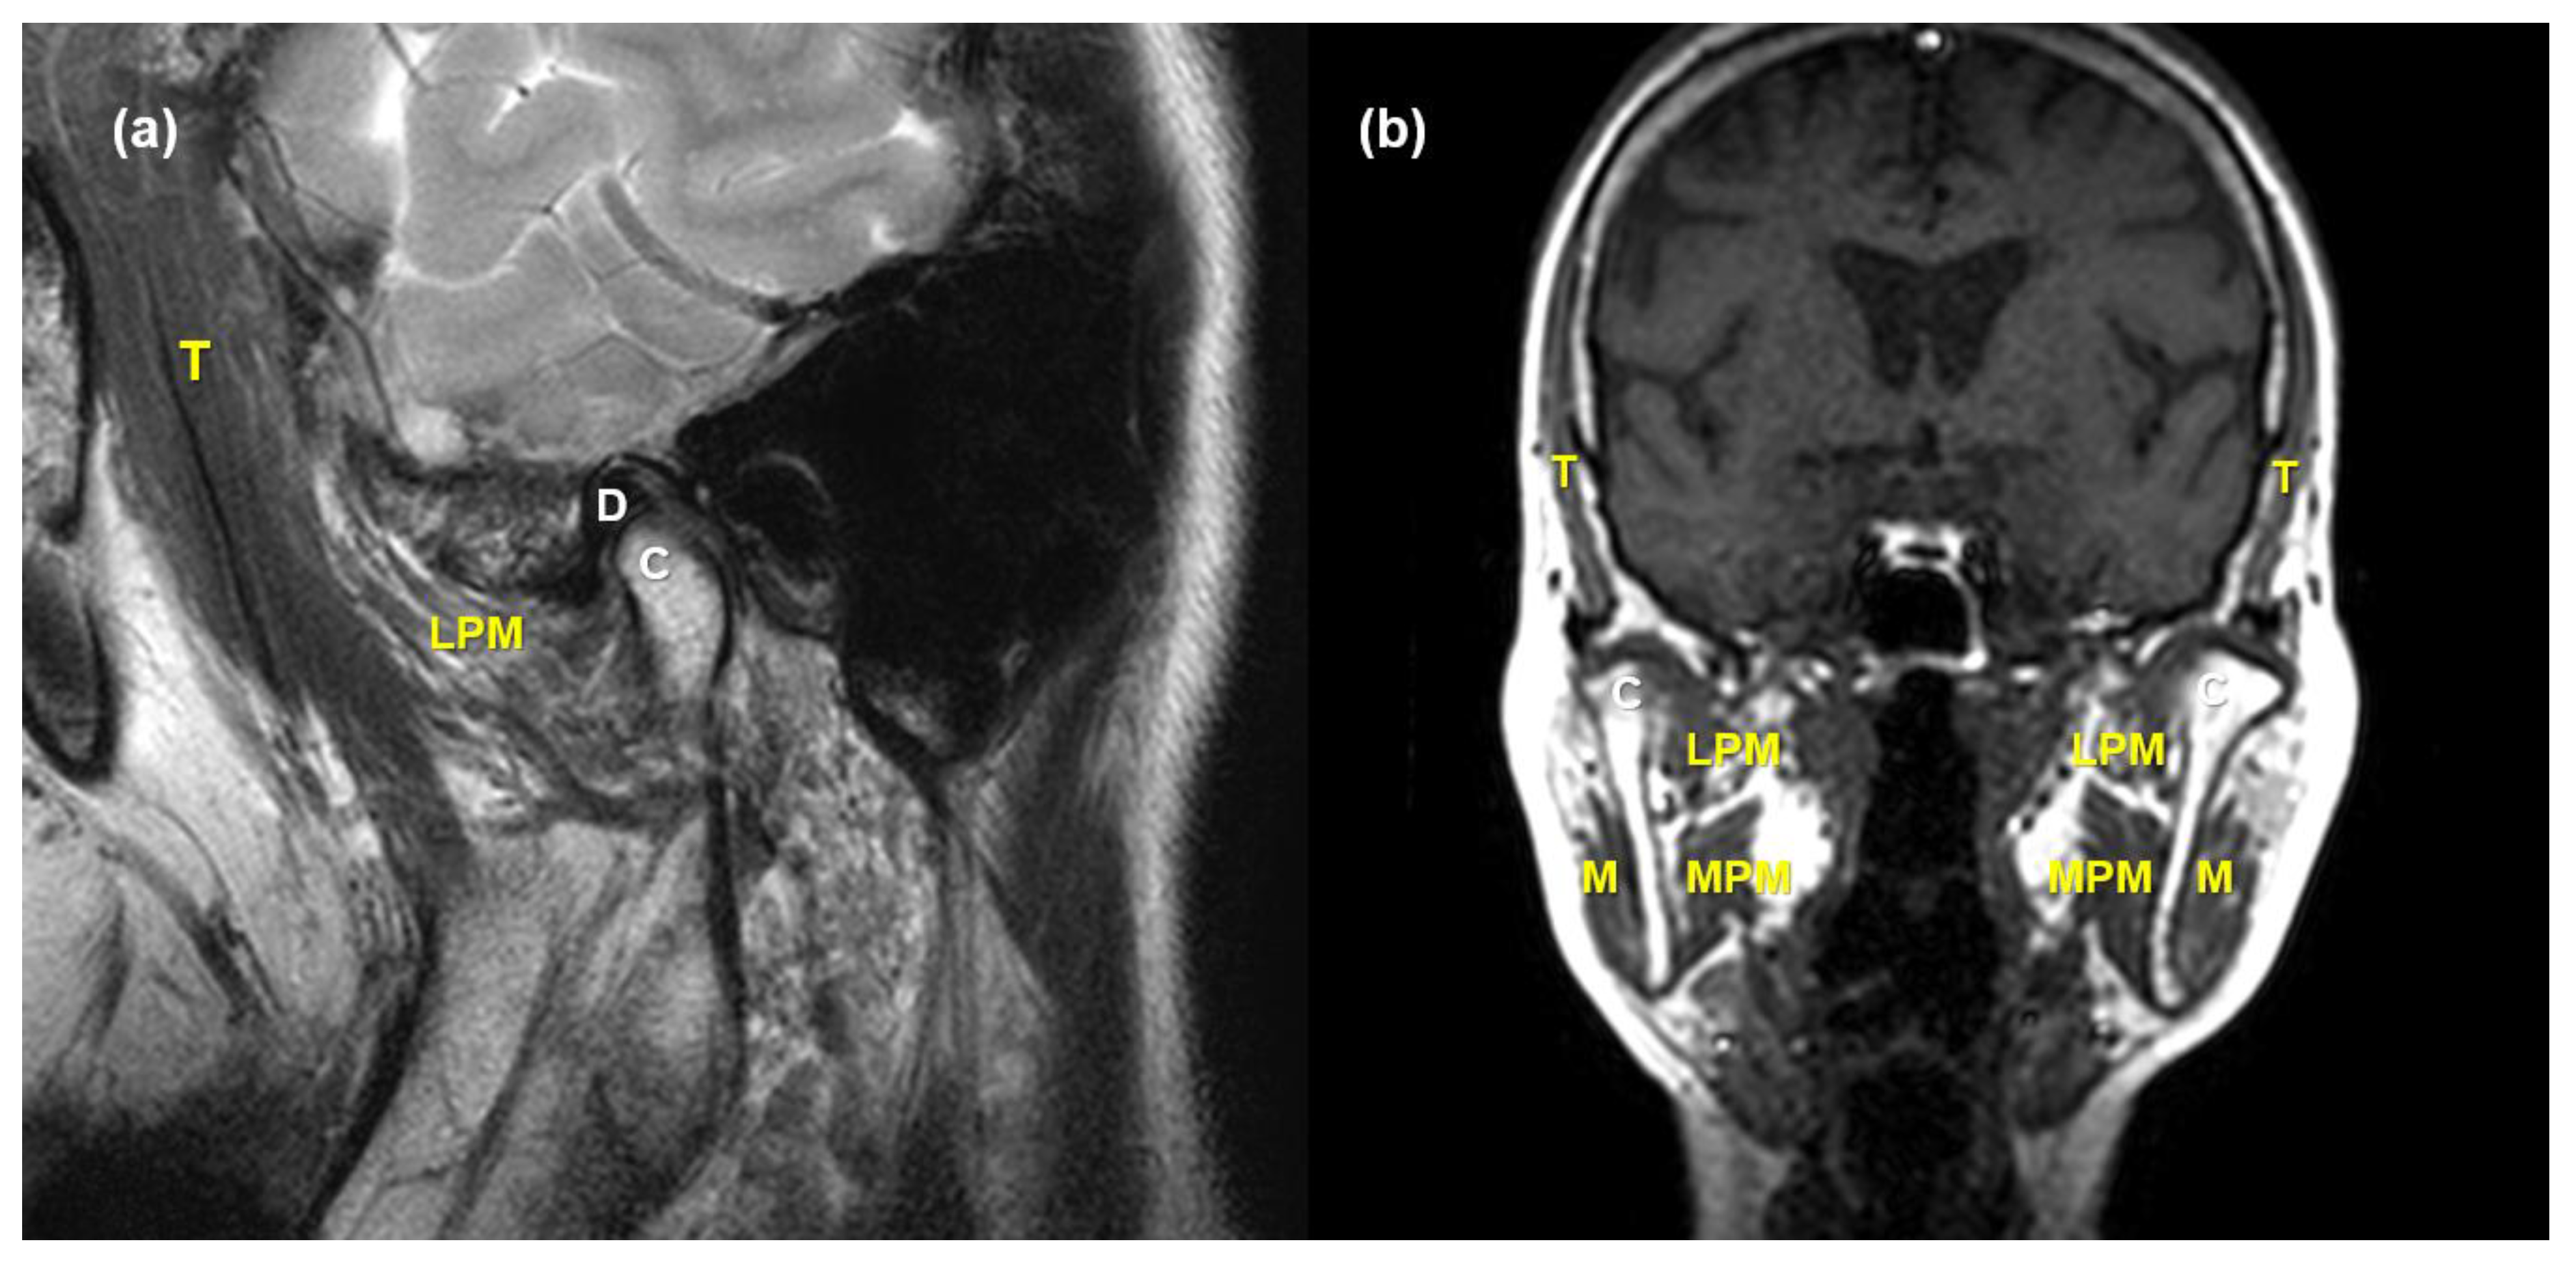

2.2. MRI Acquisition and Analysis